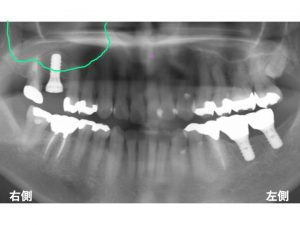

ソケットリフト法でインプラントを行なった症例です。

以下は治療前です。

上顎右側の奥から2番目が欠損しています。

ここで問題となるのが、骨の状態と上顎洞です。

以下が骨の外形です。

以下が上顎洞です。

この上顎洞は空洞なのです。

そのため、骨の高さが低いのです。

この状態では、短いインプラントしか埋入できません。

できれば長いインプラントの方がいいです。

そのため、上顎洞内に人工の骨を入れて、

上顎洞を挙上させます。

これをソケットリフト法と言います。

以下が先日行った治療後です。

実際の上顎洞を書いてみましょう。

ここがソケットリフト法で、上顎洞を挙上した部分です。

このように長いインプラントを埋入する工夫があるのです。